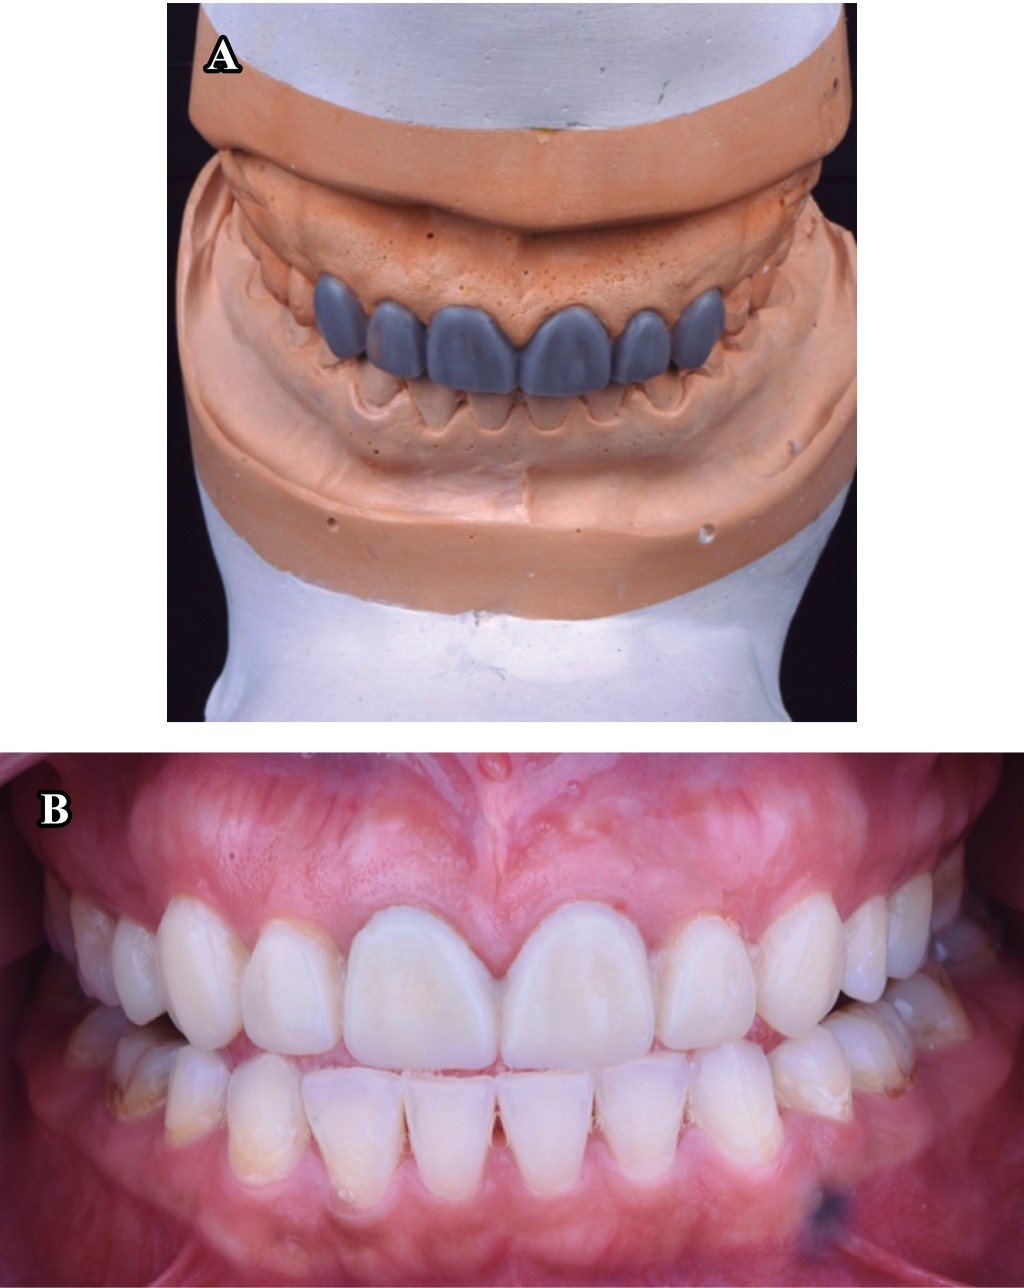

El plan de tratamiento requirió de un trabajo interdisciplinario en el que se indicó tratamiento de conductos y coronas de disilicato de litio (e.max, Ivoclar Vivadent) en los incisivos centrales y laterales superiores; carillas del mismo material en los caninos superiores izquierdo y derecho (Figura 1). Para iniciar el tratamiento se tomaron modelos de estudio, registro de mordida (Occlufast, Zhermack) y arco facial para montar los modelos en un articulador semiajustable (PCH-Panadent) (Figura 2). Posteriormente se realizó encerado diagnóstico para la confección de un Mock-up (Figura 3), en donde se evalúa la función de la nueva guía anterior establecida y deben ser realizadas pruebas de fonética y estética.

Para el acondicionamiento del diente, se grabó el esmalte con ácido ortofosfórico 37% durante 20 segundos, seguido de un lavado con agua para posteriormente aplicar un adhesivo universal (Ivopen, Ivoclar). Se procedió a cementar las restauraciones con cemento Variolink Esthetic LC (Ivoclar Vivadent) fotocurándolo durante 3 segundos antes de retirar excedentes y para realizar un fotocurado final de 20 segundos por cada cara libre. Finalmente, se fotocuró sobre una capa de glicerina para eliminar la capa inhibida por oxígeno. Se puede observar un cambio estético (Figura 7) y funcional con el restablecimiento de la guía anterior (Figura 8) en comparación con la situación inicial, además se realizó un guarda oclusal con acrílico termocurado.